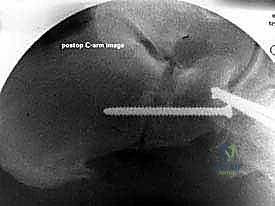

إطالة العمود الجانبي للقدم، أو قطع عظم إيفانز، هو إجراء جراحي حيوي لتصحيح تشوه القدم المسطحة المكتسبة الناتج عن قصور الوتر الظنبوبي الخلفي. يهدف إلى استعادة قوس القدم وتخفيف الألم وتحسين وظيفة القدم، ويتم على يد خبراء مثل الأستاذ الدكتور محمد هطيف.

في هذا الدليل المرجعي، سنسلط الضوء بشكل مكثف على الحل الجراحي المتقدم والفعال المعروف باسم إطالة العمود الجانبي للقدم (Lateral Column Lengthening)، وتحديداً التقنية الجراحية الدقيقة المسماة "قطع عظم إيفانز" (Evans Osteotomy). يُعد هذا الإجراء حجر الزاوية في استعادة الميكانيكا الحيوية الطبيعية للقدم، وإعادة بناء القوس المنهار، وتخفيف الألم بشكل دائم.

* الأشعة السينية (X-rays) مع تحمل الوزن: ضرورية لتقييم درجة انهيار القوس وزوايا العظام (مثل زاوية تالونافيكولار Meary's Angle).